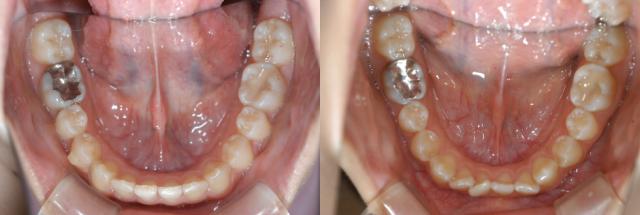

²èÁü¤Ï

¥¤¥ó¥Ó¥¶¥é¥¤¥óÁõÃå»þ

½ÑÁ°½Ñ¸å